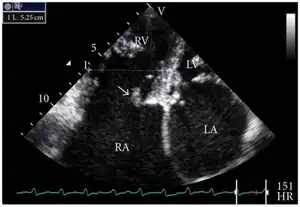

Definitive diagnosis is made by echocardiogram, which is capable of measuring both the presence and the severity of the TR, as well as right ventricular dimensions and systolic pressures.[12]

Transthoracic echo: TR (arrow) -